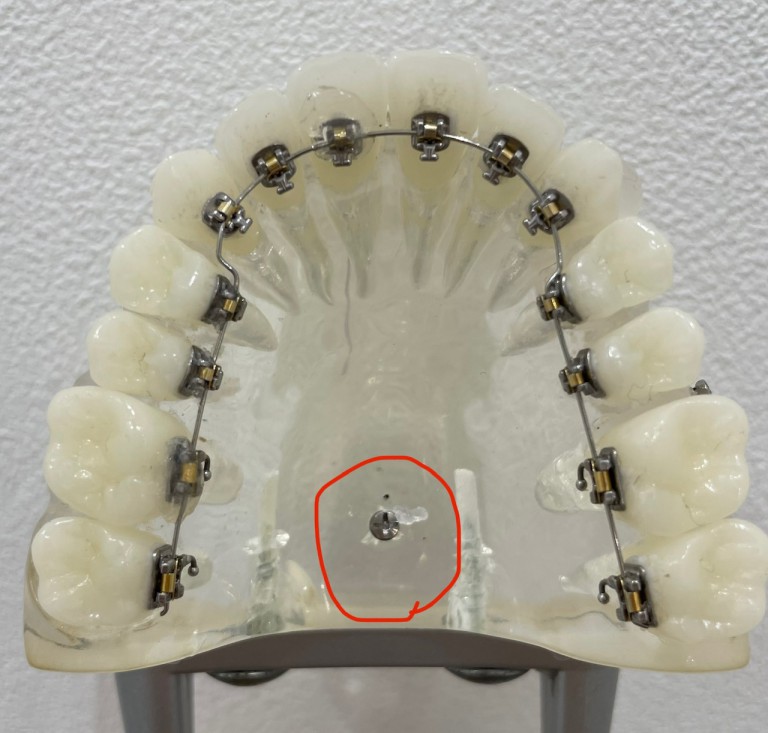

インプラント(アンカースクリュー)矯正|大阪府枚方市の辻村, 歯科矯正用アンカースクリューを用いた 矯正歯科治療クインテッセンス出版先生の臨床を大幅に広げる医療アイテム、それがアンカースクリューである。アンカースクリューを使えば、傾斜した歯のアップライト、対合歯を失ったために挺出した歯や歯列の圧下、残根を利用するための挺出、歯の近遠心方向への移動などのLOT(限局矯正)が簡単にできてしまう。一般臨床医のマストアイテム。本書は、矯正歯科医のエキスパートが一般臨床家のためにアンカースクリューの利用方法をわかりやすく解説している。保田 好隆定価: ¥ 10560(税込)書き込みなし中古品にご理解ある方、よろしくお願いします。

歯科矯正用アンカースクリューを用いた 矯正歯科治療クインテッセンス出版先生の臨床を大幅に広げる医療アイテム、それがアンカースクリューである。アンカースクリューを使えば、傾斜した歯のアップライト、対合歯を失ったために挺出した歯や歯列の圧下、残根を利用するための挺出、歯の近遠心方向への移動などのLOT(限局矯正)が簡単にできてしまう。一般臨床医のマストアイテム。本書は、矯正歯科医のエキスパートが一般臨床家のためにアンカースクリューの利用方法をわかりやすく解説している。保田 好隆定価: ¥ 10560(税込)書き込みなし中古品にご理解ある方、よろしくお願いします。